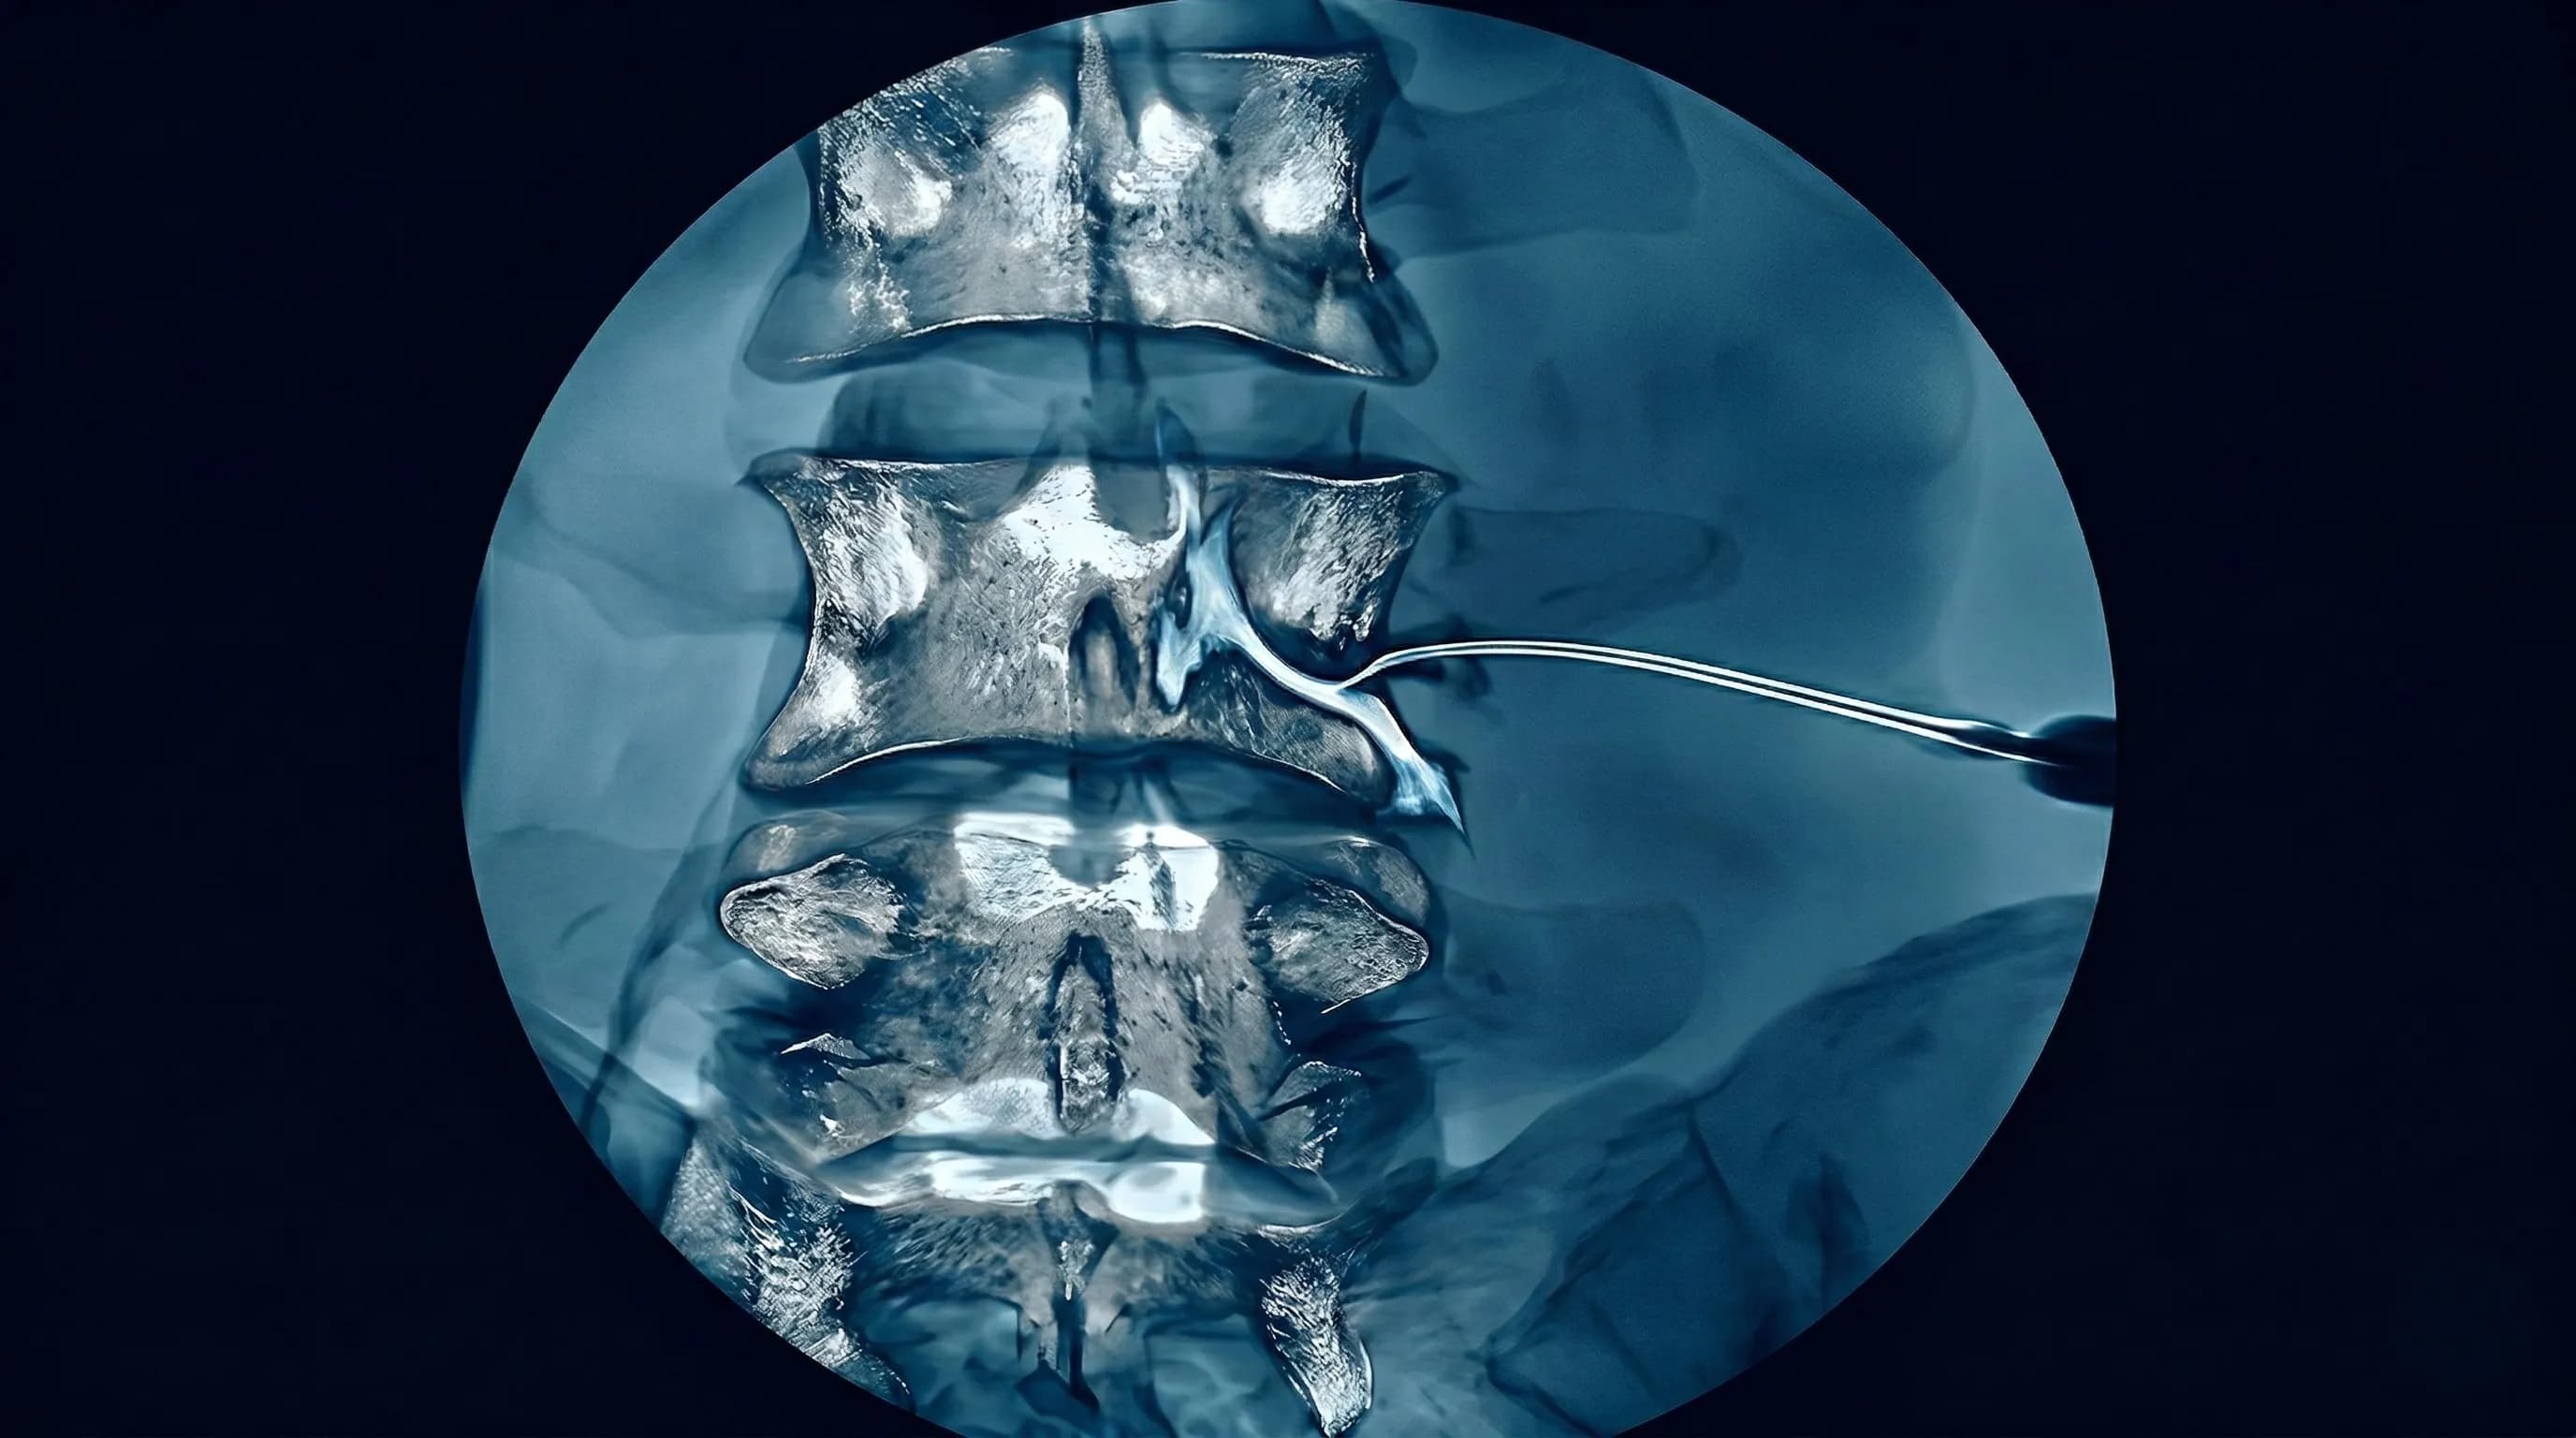

Procedimento de infiltração guiada por imagem (fluoroscopia ou tomografia) onde introduzimos anestésico local e corticoide diretamente no forame intervertebral lombar — o túnel de saída onde a raiz nervosa (L2 a S1) abandona a coluna. Diferente do bloqueio epidural comum que fica no espaço geral, o transforaminal é um "tiro cirúrgico" preciso no ponto exato da inflamação.

2️⃣ Localização: Fluoroscopia oblíqua (15-25 graus) até visualizar o "Scotty Dog" (silhueta do pedículo como orelha do cachorro). O forame é a "cabeça" do cachorro.

3️⃣ Inserção: Anestesia local cutânea, agulha espinhal de 22G ou 25G ( Quincke ou Whitacre) introduzida no trajeto subpedicular, avançando até o ponto médio do forame.

- Contraste: 0,5-1 ml de contraste iodado não-iônico mostrando o padrão "batimento de asas" (espalhamento ao redor da raiz) sem vascularização (linha escura = artéria)